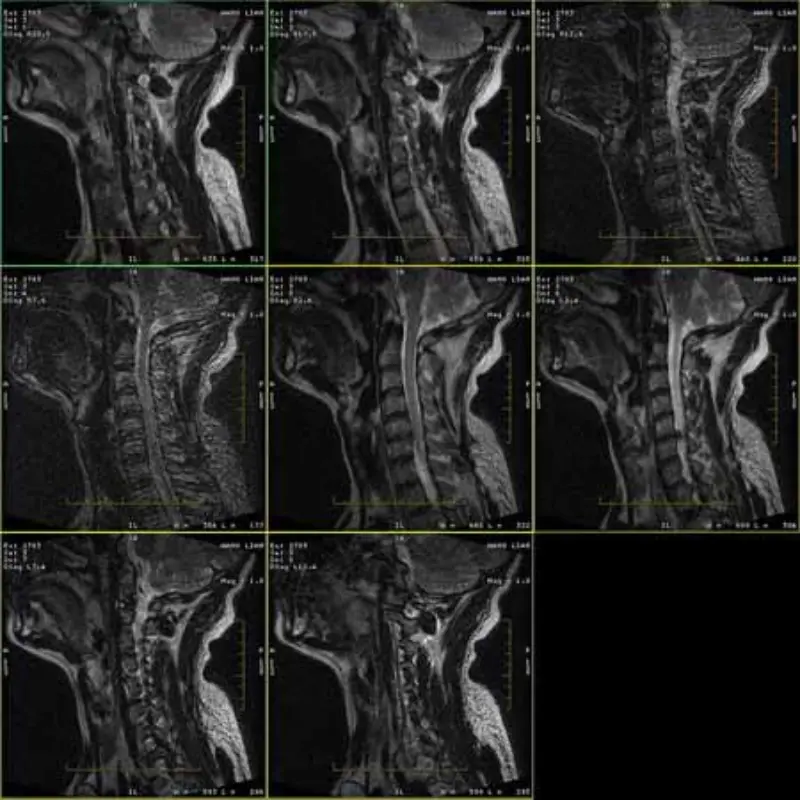

Bildene av FRFSE- og GRE-protokollene har spøkelsesbilder og noen ganger vises bilder med lav SNR i én serie. Men SE-protokollbilder er normale.

Vennligst se vedlagt bilder.